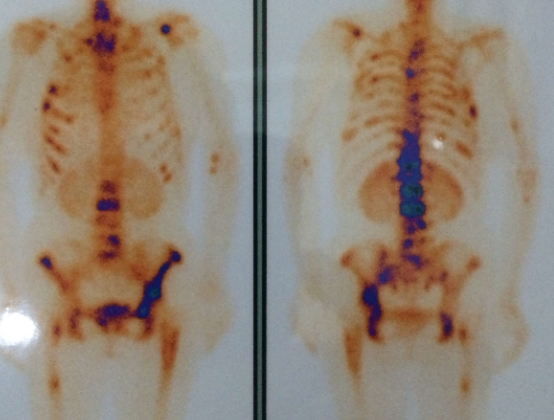

放射性核素全身骨扫描是诊断骨转移的主要手段,包括X线、CT、MRI(磁共振)、ECT(放射性核素骨扫描)、PET-CT(正电子发 射型计算机断层显像)等。

ECT能够早期筛查全身骨转移,PET-CT则能显示全身脏器及骨转移情况。